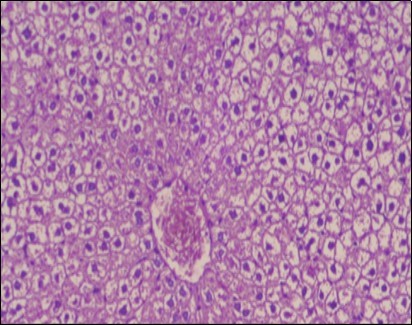

The histological examination of the livers of control rats feeding standard diet showed normal architecture hepatocytes, blood sinusoid and central vein, figure 6. The rats which were fed on a (HFD), showed swollen hepatocytes with vacuolated cytoplasm filled with fatty infiltration, congested central vein and disappearance of blood sinusoids, figure 7. By comparison, the liver of rats that were treated by fennel after obesity and control mice observed nearly normal of the hepatocytes with eosinophilic cytoplasm, central vein and clear blood sinusoids and more bi-nucleated cells, figure 8. While examination of rats' liver that were treated by Ator and after the obesity appears, they showed mild fatty change in hepatocytes, few hepatocytes retain is eosinophilic cytoplasm and central vein figure 9. Liver of rats that were treated by fennel and Ator after obesity and control rats are showing nearly normal hepatocytes figure 10.

Figure 7.Photomicrograph of liver section of obese rat showing swollen hepatocytes with vacuolated cytoplasm filled with fatty infiltration, congested central vein and disappearance of blood sinusoids, (H&E) (40X).